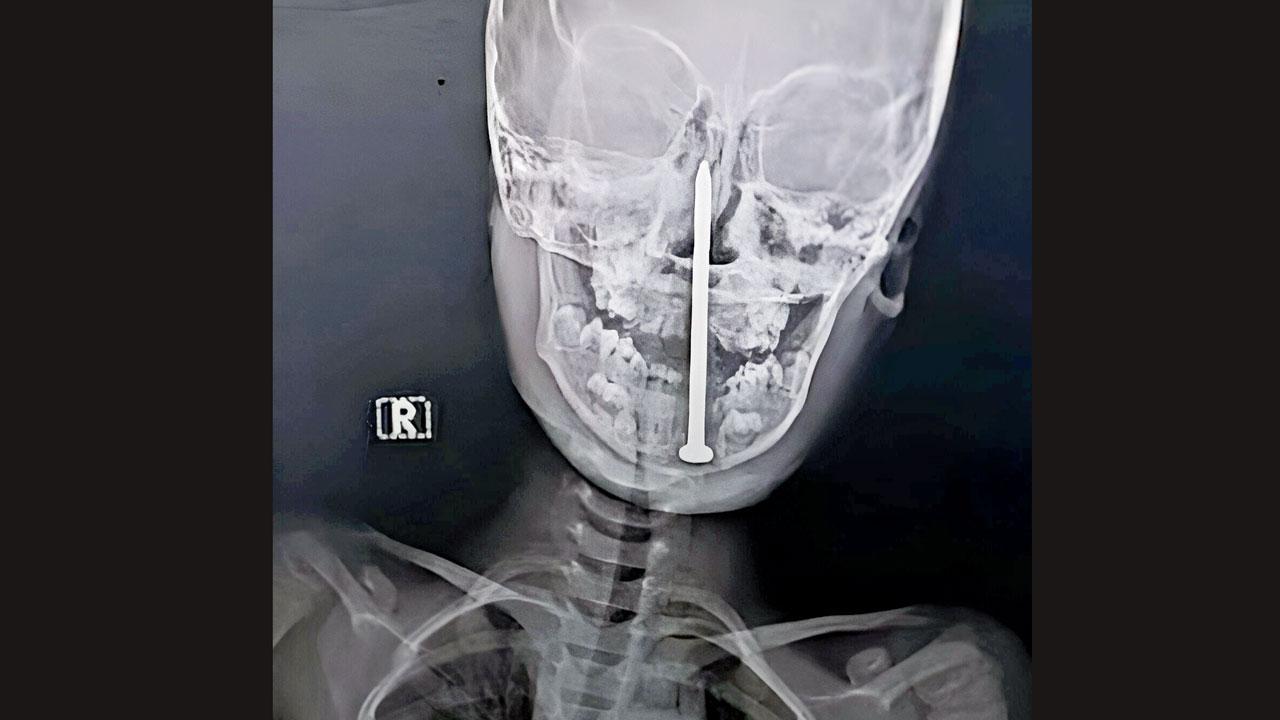

ઉત્તર પ્રદેશના લખનઉની કિંગ જ્યૉર્જ મેડિકલ યુનિવર્સિટીના ટ્રૉમા સેન્ટરમાં ડૉક્ટરોની એક ટીમે ખૂબ જ ક્રિટિકલ કહેવાય એવી સર્જરી કરીને સાત વર્ષના બાળકનું જીવન બચાવ્યું હતું. વાત એમ છે કે આ હૉસ્પિટલમાં નવાજપુર ગામથી સાત વર્ષના એક બાળકને અત્યંત ગંભીર સ્થિતિમાં લાવવામાં આવ્યું હતું. બાળક રમતું હતું ત્યારે રમતાં-રમતાં નીચે પડ્યું હતું એ વખતે નીચે પડેલો ખીલો તેની ગરદનમાં ઘૂસી ગયો હતો. ગરદનની નસોને ચીરીને ખીલો મગજના અત્યંત સંવેદનશીલ ભાગ સુધી પહોંચી ગયો હતો. બાળકની ગરદનના પાછળના ભાગમાં આઠ સેન્ટિમીટર લાંબો લોખંડનો ખીલો ઘૂસી ગયો હતો જે સીધો મગજ સુધી પહોંચ્યો હતો. જો આ ખીલો કાઢવામાં તસુભાર પણ ગરબડ થાય તો બાળકનું મગજ ડૅમેજ થઈ શકે એમ હતું. જોકે હૉસ્પિટલના નિષ્ણાતોની ટીમે જટિલ સર્જરી કરીને ખીલો કાઢ્યો હતો. આ સર્જરી મેડિકલ ક્ષેત્રમાં સીમાચિહ્નરૂપ છે.

બાળકની ગરદનના પાછળના ભાગમાં આઠ સેન્ટિમીટર લાંબો લોખંડનો ખીલો ઘૂસી ગયો હતો

આ ખીલો કાઢવામાં તસુભાર પણ ગરબડ થાય તો બાળકનું મગજ ડૅમેજ થઈ શકે એમ હતું. જોકે હૉસ્પિટલના નિષ્ણાતોની ટીમે જટિલ સર્જરી કરીને ખીલો કાઢ્યો હતો